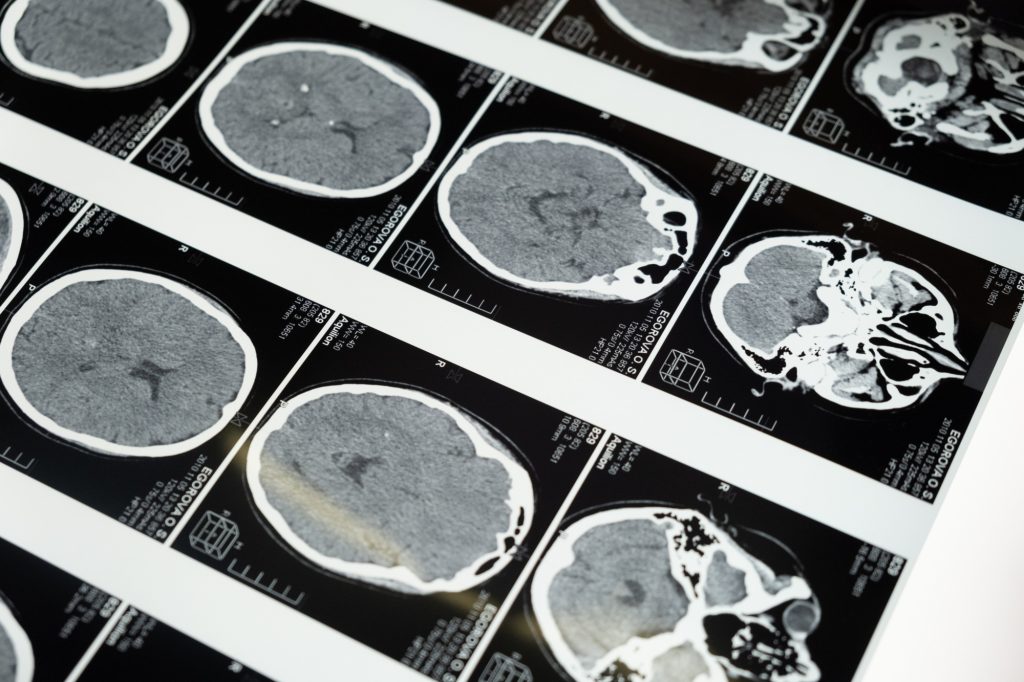

Η Gianna επισκέφτηκε νευρολόγο τον Νοέμβριο του 2022 και μετά από μία σειρά εξετάσεων οι γιατροί ανακάλυψαν ότι δεν υπήρχε ηλεκτρική δραστηριότητα στον δεξιό κεντρικό λοβό.

Είχε μόλις διαγνωστεί με άνοια.